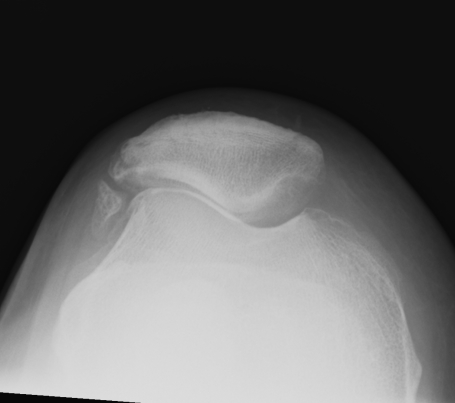

Lateral Xray

2. Assess Trochlea Dysplasia

Dejour Crossover Sign

- lateral x-ray at 30o with condyles superimposed

- identify base of trochlea

Normal

- clearly defined trochlea groove

Abnormal / Crossover

- line of floor of trochlea crosses lateral lip of condyle

- indicates trochlea is deficient proximally